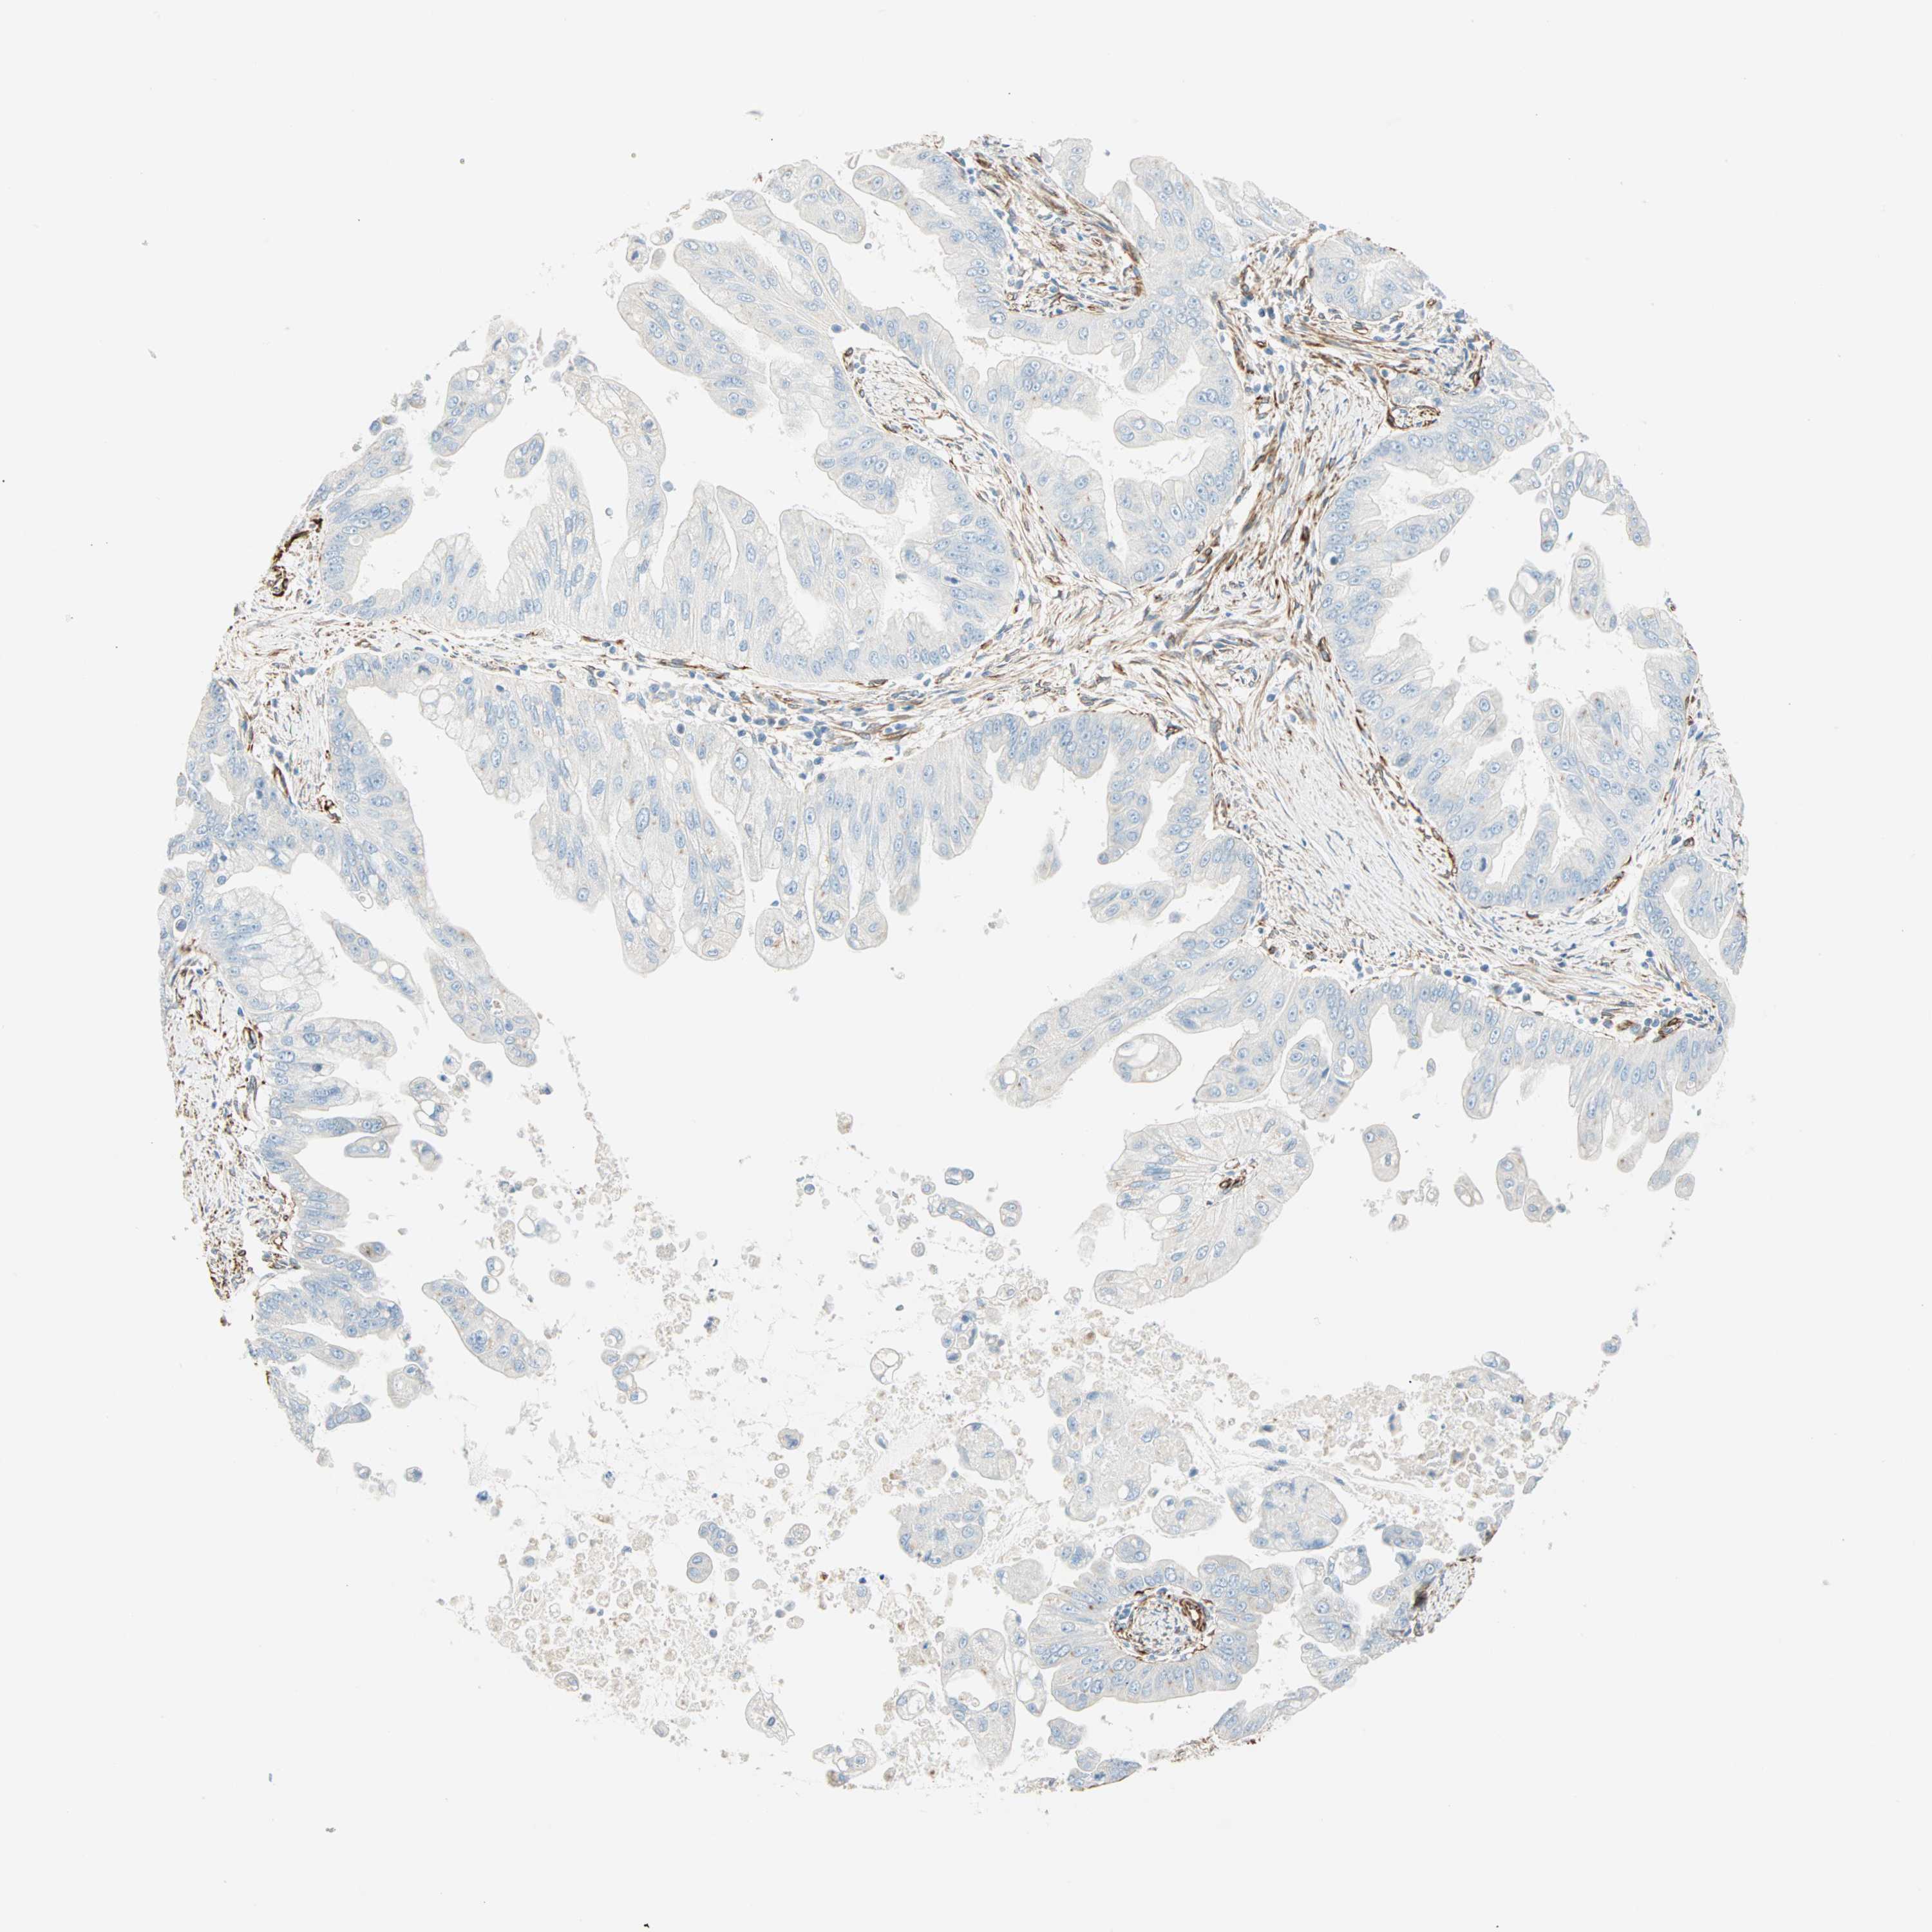

PANCREATIC CANCER - Protein expressioni

A mouse-over function shows sample information and annotation data. Click on an image to view it in a full screen mode. Samples can be filtered based on level of antibody staining by selecting one or several of the following categories: high, medium, low and not detected. The assay and annotation is described here.

Note that samples used for immunohistochemistry by the Human Protein Atlas do not correspond to samples in the TCGA dataset.

Antibody stainingi

Antibody staining in the annotated cell types in the current human tissue is reported as not detected, low, medium, or high, based on conventional immunohistochemistry profiling in selected tissues. This score is based on the combination of the staining intensity and fraction of stained cells.

Each image is clickable and will lead to virtual microscopy that enables deeper exploration of all samples and also displays staining intensity scores, fraction scores and subcellular localization as well as patient and tissue information for each sample.

Antibody HPA007007

Antibody HPA026111

Antibody CAB005889

Antibody CAB058692

Staining

High

Medium

Low

Not detected

Intensity

Strong

Moderate

Weak

Negative

Quantity

>75%

75%-25%

<25%

None

Location

Nuclear

Cytoplasmic/membranous

Cytoplasmic/membranous,nuclear

Adenocarcinoma, NOS

Adenocarcinoma, metastatic, NOS